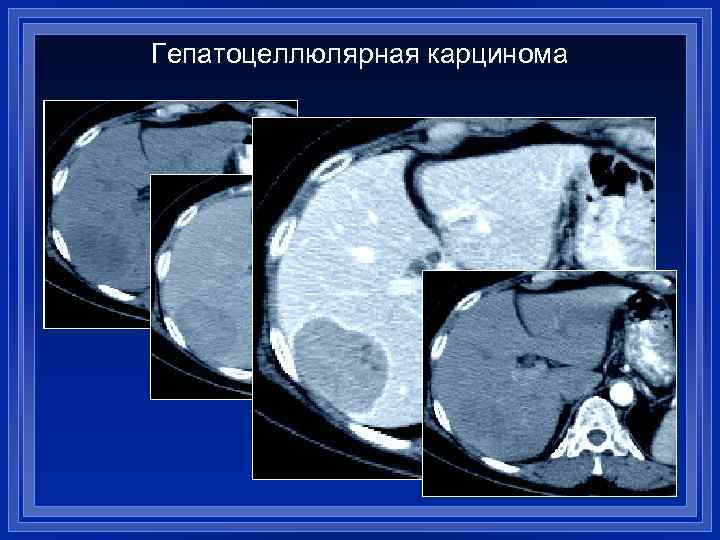

Гепатоцеллюлярная карцинома